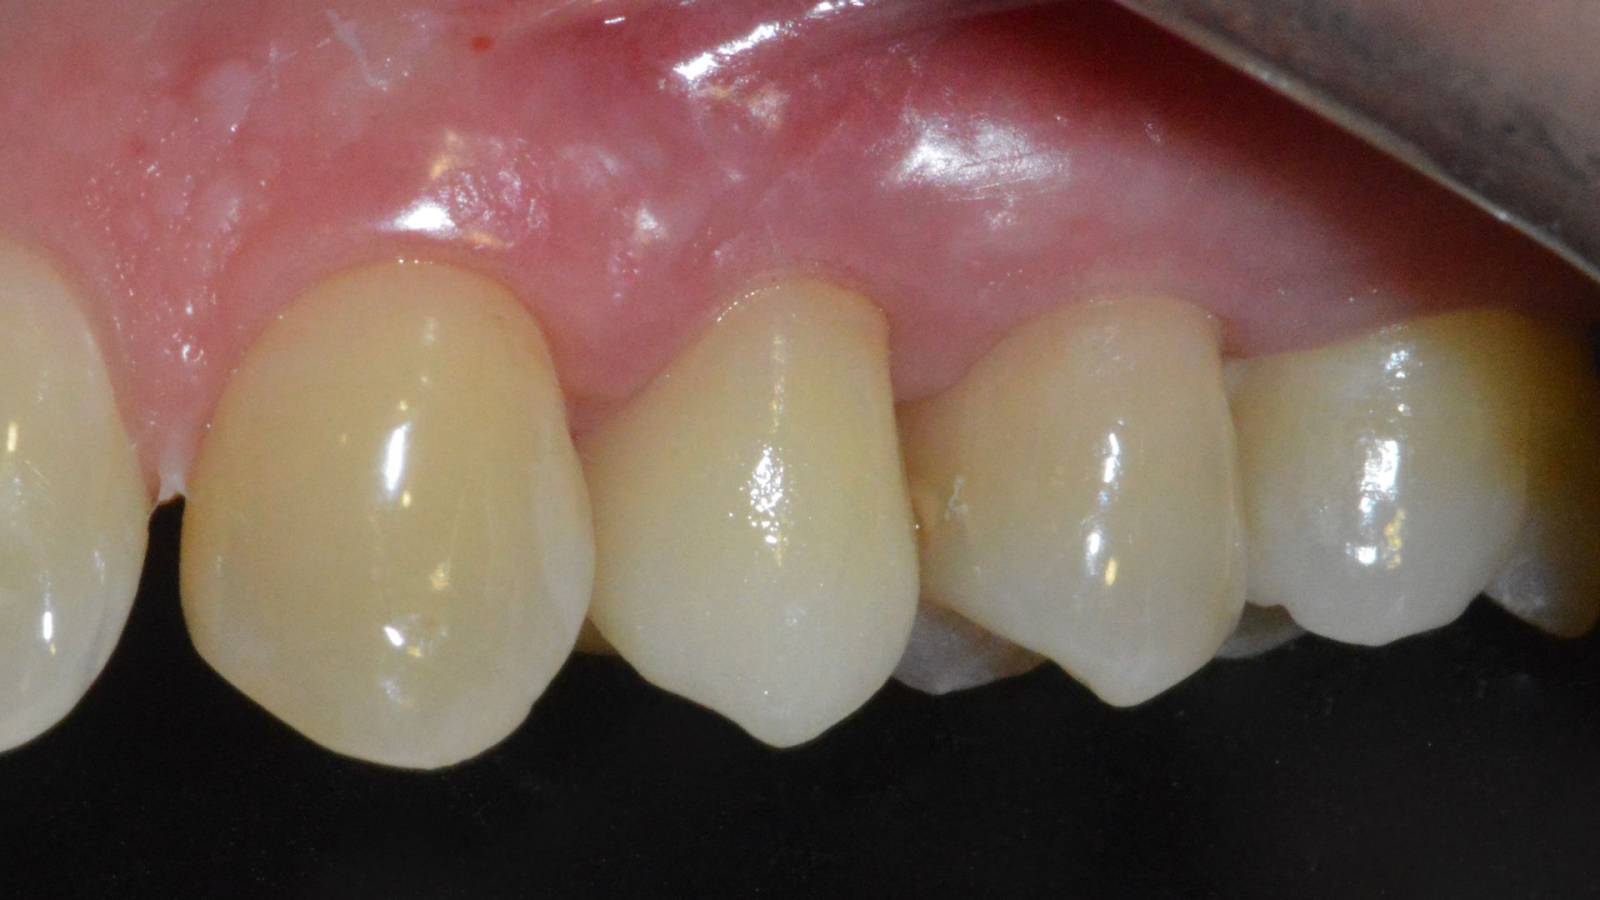

Upper central incisors, in 4 hours

Four IPS e.max CAD single crowns

The restoration with all-ceramic crowns did not require subgingival preparation to cover the margin and no dark metal shadows disturbed the esthetics. With CEREC Primescan and CEREC Primemill patients receive a high-quality all-ceramic restoration faster than ever before.

Before: Inadequate fillings on teeth 12-22, an uneven gingival line on 12 and 11 and incisal edges severely eroded.

After: Four highly esthetic and individualized lithium disilicate ceramic crowns.

Claudia Scholz

Kiel, Germany